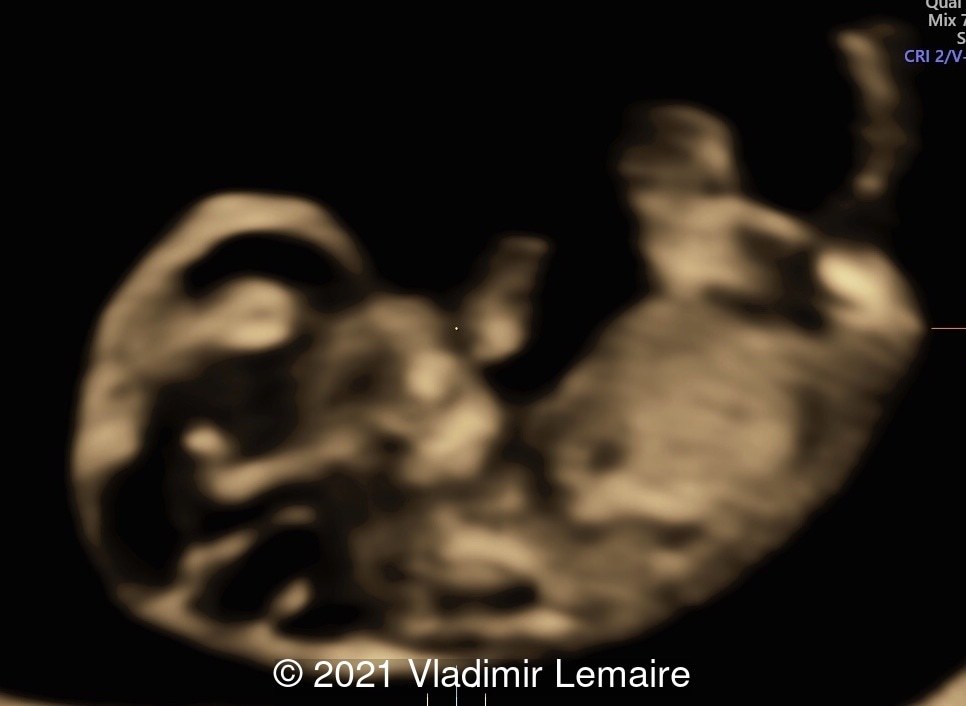

A rendered image of the same embryo in Silhouette mode.

Image 3 A rendered image of the same embryo in Silhouette mode.